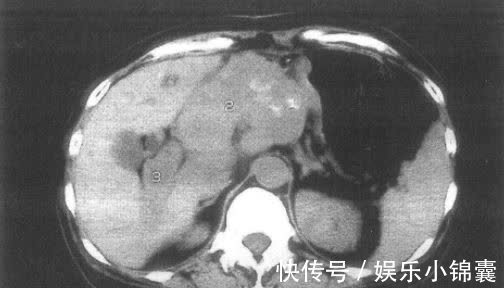

于是担心是食物中毒的母女俩,双双赶去了医院,可经过检查后,医生在他们的胃部发现了肿瘤存在,最终确诊其为胃癌。得知这个结果后母女俩都很震惊,她们不敢相信:平日里身体好端端的,怎么就会患上癌症呢?